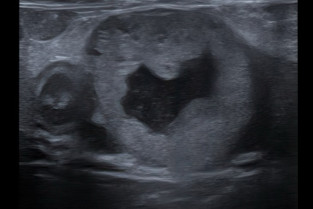

- identifier par l’imagerie des nodules et masses pancréatiques ;

- réaliser une échographie des petits organes ;